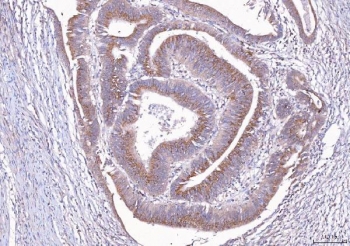

IHC staining of FFPE human rectal cancer tissue with ALDH3A1 antibody. HIER: boil tissue sections in pH8 EDTA for 20 min and allow to cool before testing.